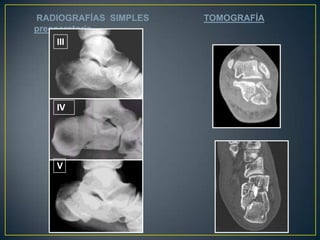

IIIIVVRADIOGRAFÍASSIMPLES 		    TOMOGRAFÍApreoperatoria

TAC

II  BTC  preoperatoriaIncongruencia subtalica  post.   :  90 %Conflicto maleolar externo            :  80 %Lesión calcáneo-cuboidea             :  40 %

Crosby y fitzgibbon y de Sanders Tipo I son fracturas no desplazadas. Tipo II son dos partes o dividir las fracturasTipo III son de tres partes o las fracturas de la depresión de división. Tipo IV fueron de cuatro partes o muy conminutas fracturas articulares. Basada en TAC: lesiones complejas